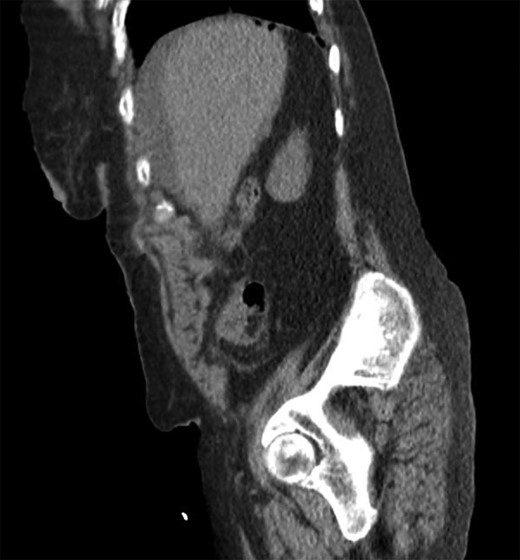

She was a former smoker with past medical history of hypertension, cerebrovascular event, hypothyroidism, and hyperlipidemia, and esophagogastroduodenoscopy and colonoscopy for gastrointestinal bleed, without past surgical history. On physical exam, she was normothermic, tachycardic, hypotensive and saturating 100% on room air. She had a distended, diffusely tender abdomen with guarding and rebound tenderness. Laboratory results were notable for leukocytosis with a left shift, chronic anemia, and acute kidney injury. Computed tomography of the chest, abdomen, and pelvis showed esophageal thickening, free air under the diaphragm, duodenal inflammation, generalized mesenteric fat stranding, free fluid in the abdomen and pelvis, and a thickened and inflamed bladder wall with irregular foci of hyperintensity within the bladder lumen and a left hydroureteronephrosis (Figs 1–3).

Sagittal computed tomography showing intra-peritoneal free air under the diaphragm.